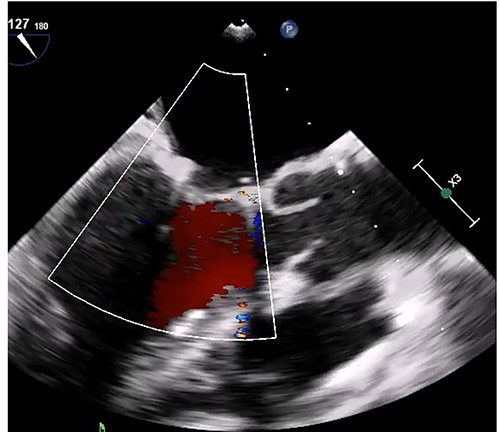

Median sternotomy was performed, and cardiopulmonary bypass was established via aortic and bicaval cannulation. Under cardiac arrest with antegrade cardioplegia perfusion, the LA was examined via the transseptal approach. The LA cavity was filled with the mass that the stalk was attached to the septal wall at the LA side, and the mass was too big and resected in pieces (Fig. 2). The mitral valve leaflet was intact, and the atrial septum was closed. Dilatated tricuspid annulus was fixed using a flexible band (Tailor Flexible band 29 mm, Abbott). After unclamping of the ascending aorta, a transesophageal echocardiogram points out moderate mitral regurgitation due to mitral annulus dilatation (Fig. 3). Cardiac arrest was performed again, and mitral annuloplasty was performed with a semi-rigid ring (Carpentier-Edwards Physio Ring II 26 mm, Edwards) via left atriotomy. His heart sinus rhythm returned to normal with successful weaning from cardiopulmonary bypass. After the transesophageal echocardiogram procedure, no evidence of the mass and residual mitral regurgitation was confirmed (Fig. 4).

Transesophageal echocardiogram after mitral annuloplasty. There was no residual mitral regurgitation.